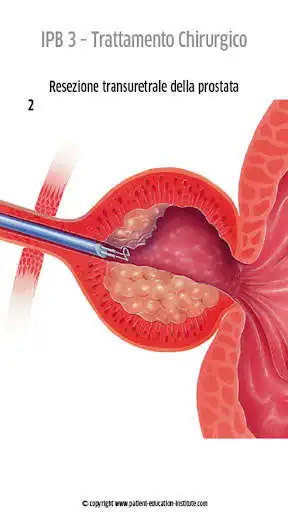

Lapp Patient Education Institute, contenente migliaia di illustrazioni mediche, costituisce un supporto visivo senza eguali che consentir agli operatori sanitari di migliorare la qualit delle conversazioni con i propri pazienti. Ogni situazione clinica si presenta in modo ben strutturato, con illustrazioni, icone e brevi testi esplicativi di facile comprensione.

La situazione di stress in cui si trovano i pazienti durante il consulto li induce a recepire le informazioni in maniera molto ridotta. Proprio per questo motivo i nostri contenuti si distinguono per la semplicit con cui ogni situazione clinica viene presentata, con numerose illustrazioni di alta qualit e di facile comprensione che supporteranno adeguatamente le tue spiegazioni ed eviteranno il profilarsi di complicazioni non necessarie.